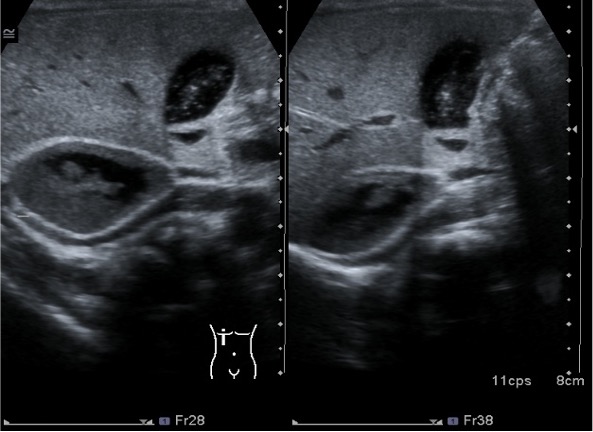

La corteza suprarrenal es hipoecogénica, es muy grande al nacimiento, progresivamente va perdiendo espesor, más o menos durante los dos primeros meses. En este periodo y gracias a su hipoecogenicidad es cuando este órgano es más visible. Además es reconocible en forma de «v» o «y».

La médula es hiperecogénica, cuando la corteza reduce queda la médula que al ser hiperecogénica la hace indistinguible de la grasa circundante que es hiperecogénica igual.